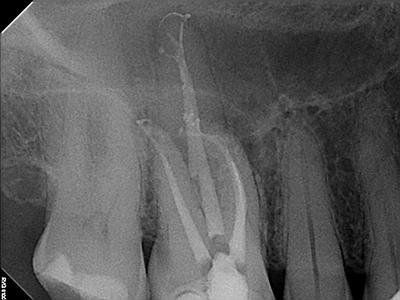

Radiographic Examination:

Tooth # 3 exhibits severe pulpal calcification, periapical radiolucencies associated with all 3 roots and severe dilaceration of the mesiobuccal root.

Conventional non-surgical root canal therapy